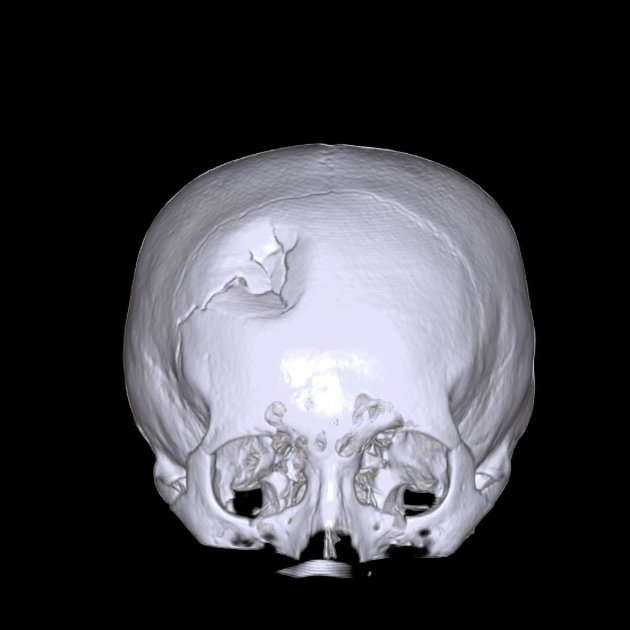

Growing Skull Fracture